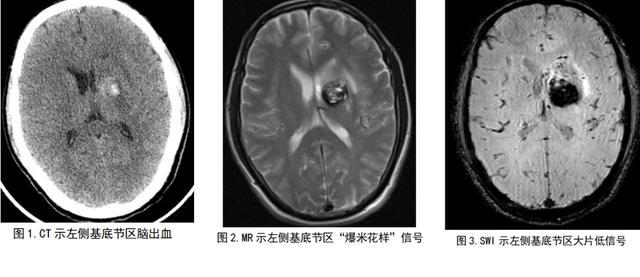

放射医学中心医师阅CT片后认为要除外血管性病变合并出血(海绵状血管瘤并出血)的可能(图1),进一步MR检查显示了左侧基底节区“爆米花”样混杂信号(图2),SWI(磁敏感)示左侧基底节区多发小点状、片状出血低信号(图3),明确了海绵状血管瘤的诊断。

湖南省第二人民医院(省脑科医院)放射科副主任吴立业介绍,脑内海绵状血管瘤CT检查部分为阴性,部分可见小点片状钙化,部分呈稍高密度灶,CT增强扫描和CTA检查通常对诊断没有明确作用,但在MR的T2WI图像上因病灶周边含铁血黄素沉积而呈典型的“爆米花样”改变,同时SWI(磁敏感)序列对病灶的显示非常敏感,可显示常规平扫阴性的小病灶,也有助于发现合并的静脉发育异常。